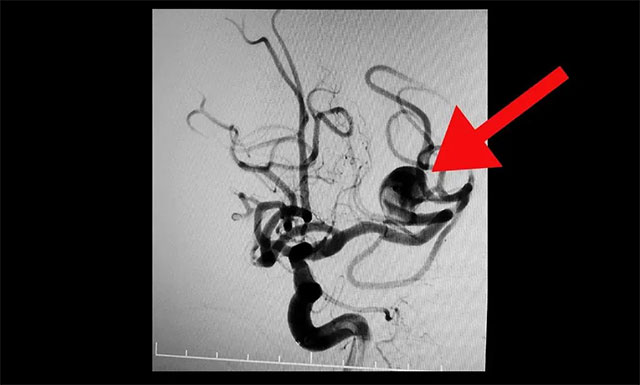

▲ DSA检查确诊:患者左侧大脑中动脉分叉部动脉瘤,瘤颈 6mm,瘤体 13 mm* 15 mm,属于大型宽颈复杂动脉瘤。该动脉瘤有持续增大并有破裂风险,手术指征明确。